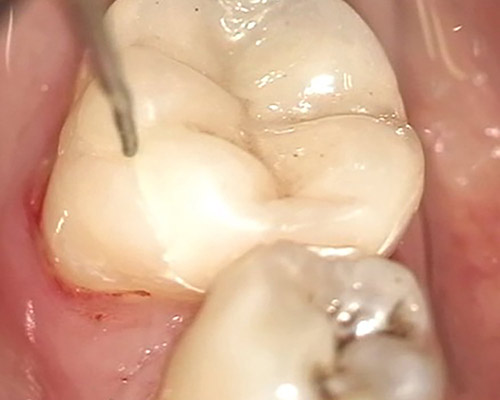

Gentle and painless treatment of dental caries and dental lesions using the most modern techniques and materials from renowned companies with emphasis on aesthetics and functional tooth restoration.

We produce photocomposite, ceramic (inlay, onlay) and amalgam fillings of the latest generations.